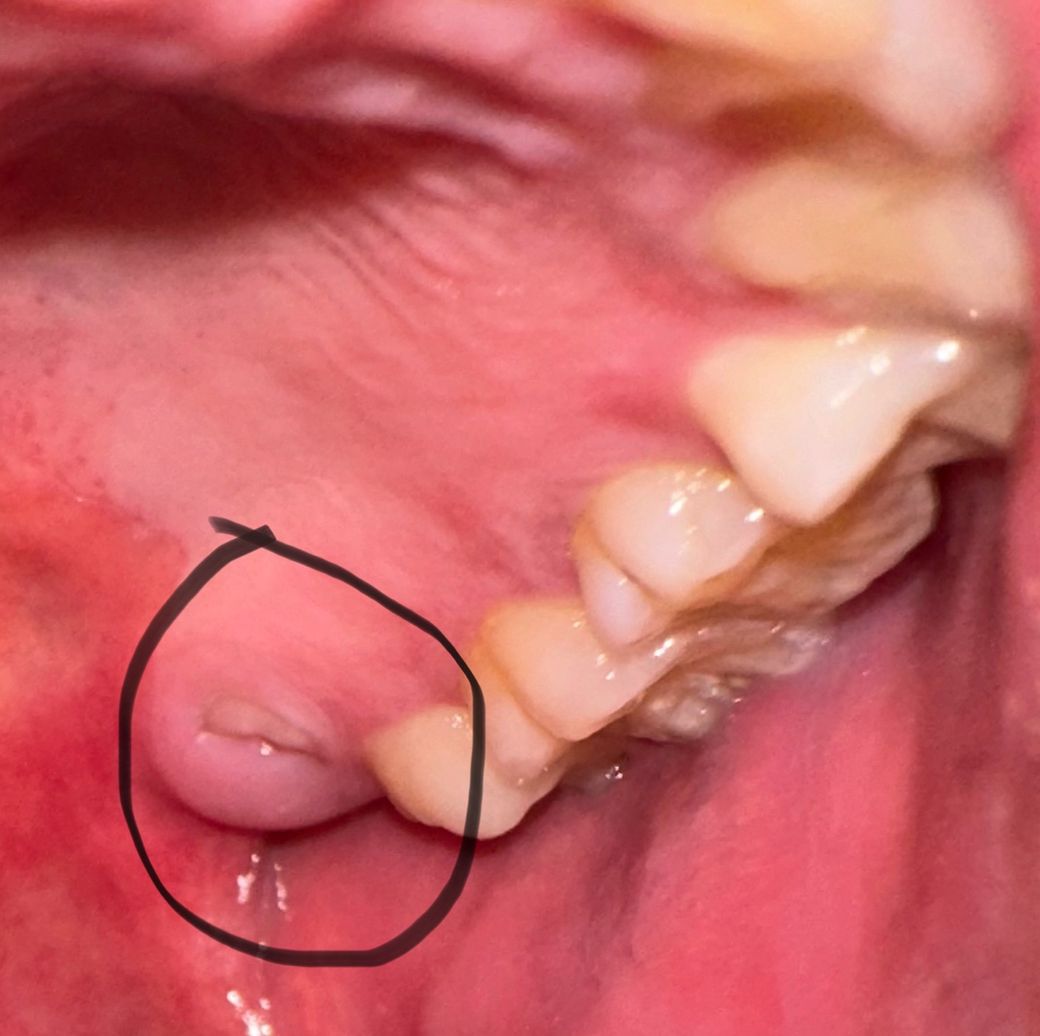

왼쪽 어금니 안쪽 잇몸에 이게 뭔가요?

이거 혹시 사랑니가 튀어나오고 있는건가요?

통증은 없는데 만지면 이빨 만지는 느낌이 납니다..;;

사진상으로는 사랑니 아니면 과잉치일 가능성이 높아 보입니다. 치과에 가셔서 엑스레이를 찍어보셔야될것같습니다.

사랑니가 잇몸을 뚫고 나오고 있는 것일 가능성이 높습니다. 해당부위기 붓기 및 통증이 동반되는 경우 바로 치과 진료를 받길 권합니다.

만졌을 때 치아 느낌이 난다면 사랑니 혹은 과잉치일 가능성이 매우 높습니다. 불편감이 있다면 해당 부위에 대한 정확한 검사를 하고 필요시 발치를 하는 것이 좋아 보입니다. 가까운 치과 방문 후 상담을 한 번 받아보시길 바랍니다.

사진만봐서는 정확히 알기 어렵습니다. 엑스레이를 찍어봐야하고요. 혀로 만져봤을때 딱딱하다면 사랑니 뿌리가 휘어져서 튀어나온 것일 수도 있을 것 같습니다.

사랑니가 맞는 것으로 보입니다. 위치가 바르지 않으니 발치하러 가시는 것이 좋아보입니다.